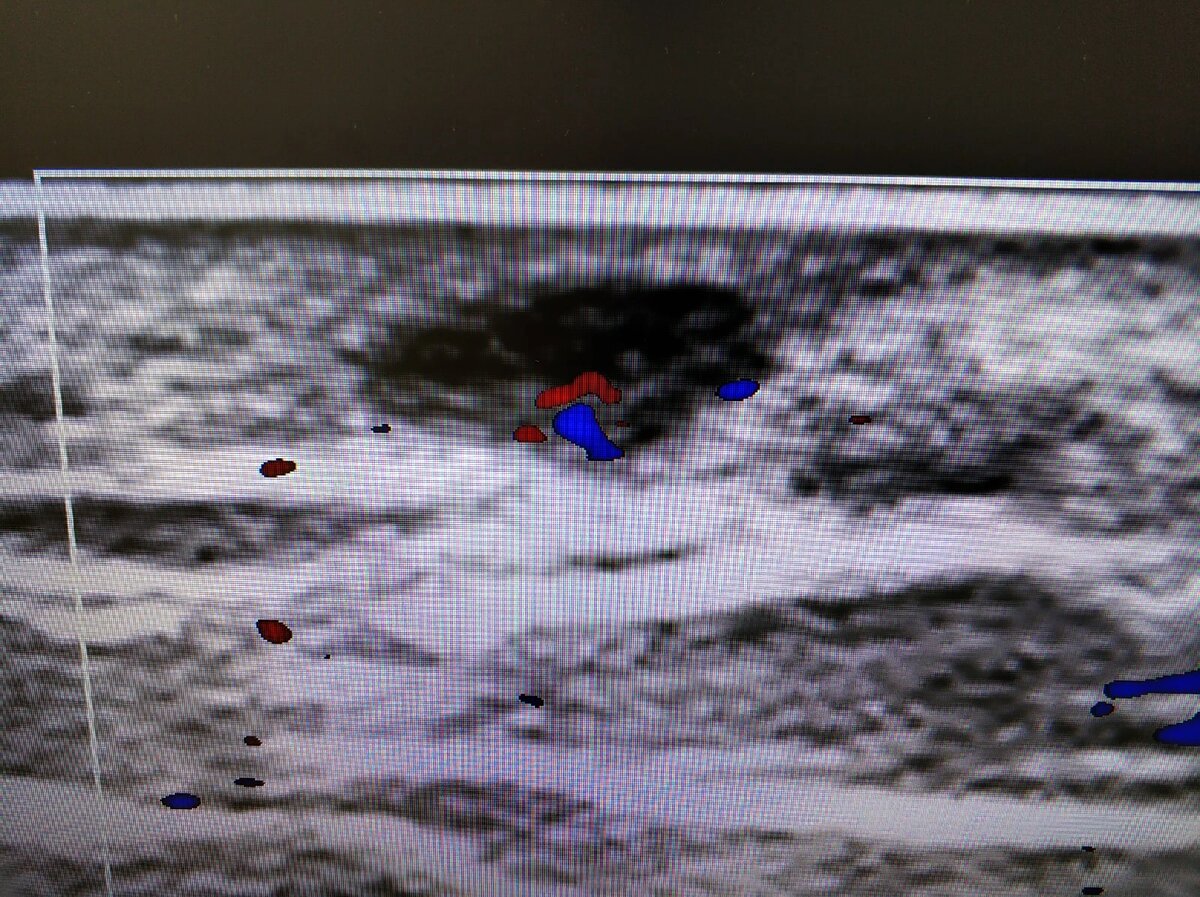

🧐Пальпируемое образование промежности в виде маленького шарика. Пациент направлен для исключения связи с прямой кишкой, а так же разобраться с природой образования.

🖼️На снимке образование овальной формы, горизонтально ориентировано, преимущественно гипоэхогенное. Расположено в дерме, немного выходит в гиподерму.

👨‍💻При снижении динамического диапазона виден гиперэхогенный компонент с единичным сосудом. Сосуд входит через одну точку, гиперэхогенный тяж к краю образования - ворота. Структура типичная для лимфоузлов.